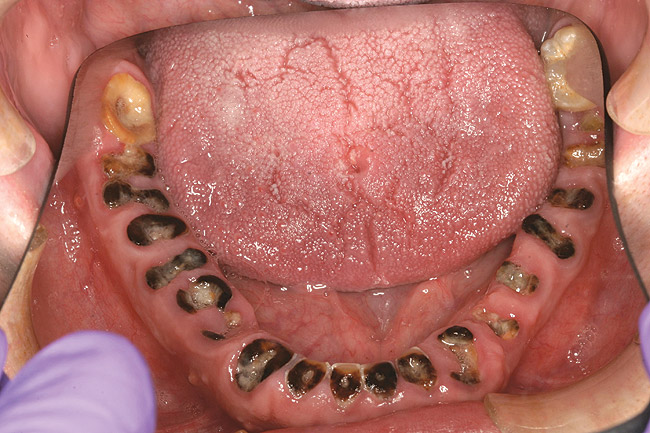

Joe soon learned how to manufacture the drug. His need for meth soon consumed his every thought. He basically lived to do more meth. He admitted that he had made some poor choices. Unfortunately once the addiction kicked in, he no longer had a choice, he had to use. This was his end result (Figure 4 through Figure 6). From these photographs, one might think that he had used the drugs his entire life; however, this progression happened over the course of only about 1 year of smoking the drug. Because of the caustic chemicals (muriatic acid, hydrochloric acid, lithium, etc) his teeth started to blacken, then break.

Figure 4  PRESENTATION CONDITION By the time Joe presented for treatment after serving time in prison and going to rehab, his teeth were completely destroyed by rampant decay. Although some teeth could have been saved, the patient chose to have all of the remaining teeth extracted in order to receive a set of full dentures.

Figure 5  PRESENTATION CONDITION By the time Joe presented for treatment after serving time in prison and going to rehab, his teeth were completely destroyed by rampant decay. Although some teeth could have been saved, the patient chose to have all of the remaining teeth extracted in order to receive a set of full dentures.

Figure 6  PRESENTATION CONDITION By the time Joe presented for treatment after serving time in prison and going to rehab, his teeth were completely destroyed by rampant decay. Although some teeth could have been saved, the patient chose to have all of the remaining teeth extracted in order to receive a set of full dentures.